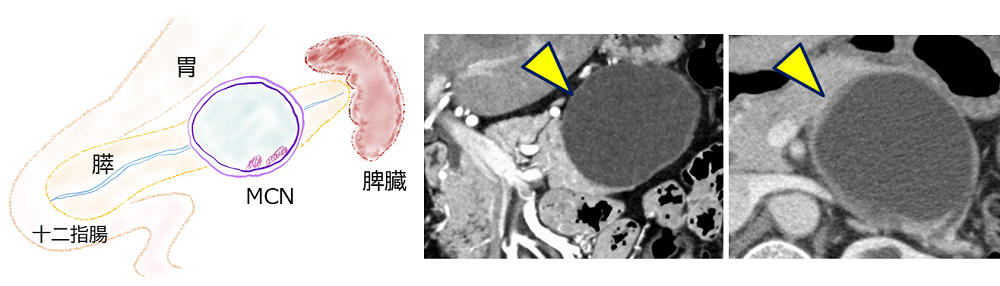

3. 粘液性嚢胞腫瘍(MCN)の外科治療

粘液性嚢胞腫瘍(mucinous cystic neoplasm)は略してMCNと呼ばれます。MCNもIPMNと同様、粘液を産生する腫瘍ですが、MCNの嚢胞は拡張した膵管ではなく、嚢胞と膵管はつながっていません(下の図3)。患者さんのほとんどは女性で、膵の体尾部に好発します。MCNの成長速度は遅く比較的おとなしい腫瘍ですが、嚢胞壁にがんができ嚢胞外に浸潤したり、リンパ節や肝など遠隔臓器に転移することもあります。浸潤がんになる前であれば転移は無く切除により治癒が得られるため、腹腔鏡下膵切除の良い適応です。大きな腫瘍や高度の浸潤がんを伴う場合には開腹手術が必要となることもあります。